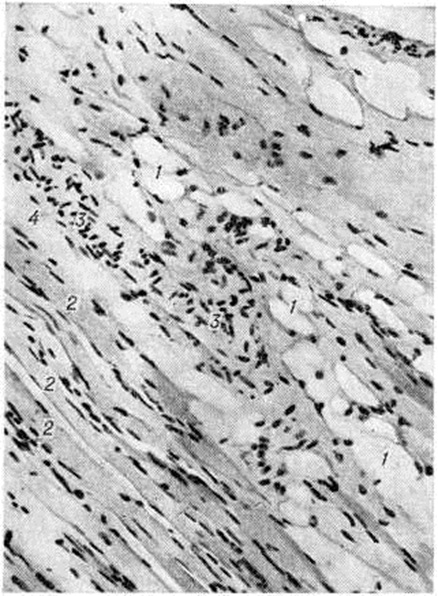

Стадия индурации (рисунок 1) характеризуется склерозом сосочкового и Сетчатого слоёв дермы с запустеванием капилляров, склерозом стенок сосудов, уменьшением количества клеток, утолщением коллагеновых пучков сетчатого слоя и гиалинозом (смотри полный свод знаний), атрофией эпидермиса и придатков кожи, склерозом и гиалинозом подкожной клетчатки. Васкулиты на этой стадии выявляются редко. Клеточные инфильтраты обычно скудные, представлены 3—5 клетками лимфоидного типа.

Поражение кожи при системной Склеродермия часто сочетается с поражением суставов, костей и мышц. При поражении суставов обнаруживается экссудативно-пролиферативный синовит (смотри полный свод знаний) с фибринозными наложениями на поверхности синовиального слоя суставной капсулы, очаговой пролиферацией синовиоцитов, единичными продуктивными васкулитами, умеренно выраженным ангиоматозом, лимфоидно-макрофагальной инфильтрацией в субсиновиальном и фиброзном слоях. Суставной хрящ при системной Склеродермия теряет эластичность, становится ломким и быстро изнашивается; отмечается околосуставной остеопороз (смотри полный свод знаний). При отсутствии признаков артрита в суставной полости фактически отсутствует синовиальная жидкость, макроскопически синовиальный слой суставной капсулы становится плотным, лишённым ворсинок. При гистологический исследовании с трудом удаётся найти её органоспецифические особенности: синовиоциты на большем протяжении отсутствуют, синовиальный слой покрыт гиалиноподобными массами, субсиновиальный слой представлен бедной сосудами фиброзной соединительной тканью с обширными полями гиалиноза. При системной Склеродермия, сопровождающейся миопатическим синдромом, гистологический исследование скелетных мышц выявляет картину хронический миозита (смотри полный свод знаний) с разнокалиберностью мышечных волокон, гидропической дистрофией и миолизом части их, периваскулярными инфильтратами из лимфоцитов, макрофагов, полинуклеаров, васкулитами, разрастанием грануляционной и фиброзной соединительной ткани в эн дои перимизии. Более характерен фиброзирующий интерстициальный миозит (рисунок 3) с выраженным склерозом, липоматозом, гиалинозом эпи и перимизия, склерозом стенок сосудов, запустеванием капиллярного русла, мелкоочаговой периваскулярной лимфоидно-макрофагальной инфильтрацией, единичными васкулитами, очаговой перифасцикулярной или диффузной атрофией мышечных волокон.

Рис. 1.

Микропрепарат кожи при системной склеродермии (стадия индурации): 1 — склероз и гиалиноз сосочкового и сетчатого слоёв дермы и подкожной клетчатки, 2 — скудная лимфоидно-гистиоцитарная инфильтрация по ходу сохранившихся капилляров, 3 — атрофия эпидермиса, 4 — атрофия фолликула волоса; окраска гематоксилин-эозином; ×120.

Рис. 3.

Микропрепарат скелетной мышцы при системной склеродермии: 1 — липоматоз перимизия, 2 — истончение мышечных волокон, з — пролиферация ядер сарколеммы, 4 — склероз перимизия; окраска гематоксилин-эозином; ×160.